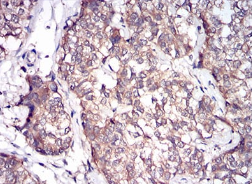

IHC    1/200 - 1/1000